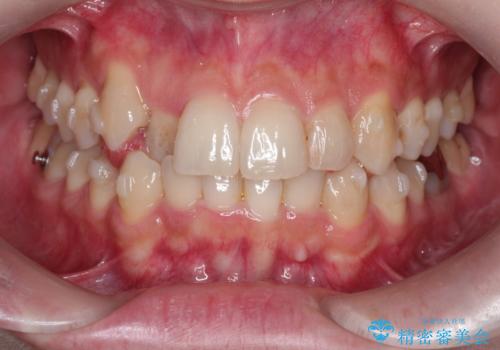

- 八重歯を治したいとのことで来院されました。

右上の犬歯が外側に飛び出して、二番目の歯が内側に入っている状態でした。

上の奥歯を後方に移動させてスペースを確保して、前歯のガタガタを改善する計画としました。